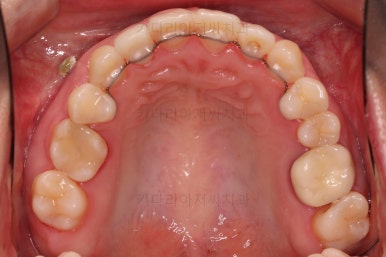

부산치과교정 키다리아저씨치과 초진 시 입안의 모습입니다.

확연히 좌우의 삐뚤어진 정도가 차이나죠.

덧니도 좌측(사진에서 보면 오른쪽) 위아래만 있는 상태고요.

좌측으로 삐뚤어져서 앞니도 좌측으로 쏠려 있는 상태였습니다.